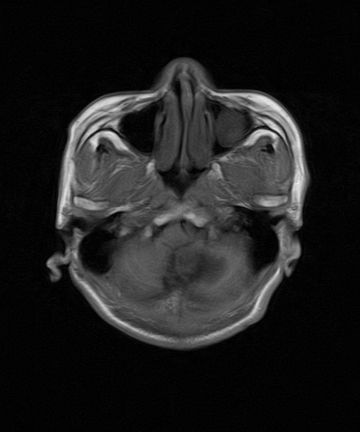

标题: MRI2064:少见病例。男性52,视力下降多年。

四脑室区见混杂信号占位影,脑室系统扩张明显,临近结构显著受压称位,患者52岁,多考虑室管膜瘤可能性大

应该是来源于小脑蚓部的占位,如血管母细瘤或星形细胞瘤

小脑血管母细胞瘤.并外压性脑积水.

小脑蚓部胶质脑膜瘤突入四脑室;肿瘤内见血管流空信号和钙化信号.

比较典型的脉络丛乳头状瘤并脑积水,鉴别小脑蚓部血管母细胞瘤。